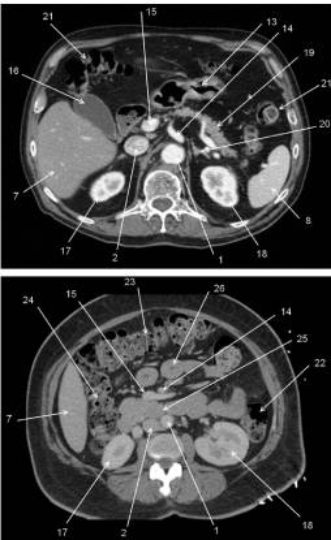

Fig. 2.3 Reconstruction en 3D volume rendering de l’aorte abdominale avec le tronc cœliaque, l’artère mésentérique supérieure et leurs branches de division (les autres branches de l’aorte abdominale ont été effacées).

1. Aorte (avec plaques d’athérome calcifiées). 2. Artère mésentérique supérieure. 3. Tronc cœliaque. 4. Artère hépatique commune. 5. Artère gastroduodénale. 6. Artère hépatique propre. 7. Branche droite de l’artère hépatique. 8. Branche gauche de l’artère hépatique. 9. Artère splénique. 10. Artère gastrique gauche.

Fig. 2.5 Vue frontale d’une séquence de cholangiopancréatographie IRM où seules les structures contenant du liquide immobile sont visibles.

1. Conduit pancréatique (de Wirsung). 2. Sphincter de l’ampoule hépatopancréatique (d’Oddi). 3. Conduit cholédoque. 4. Conduit cystique. 5. Conduit hépatique gauche. 6. Conduit hépatique droit. 7. Vésicule biliaire.